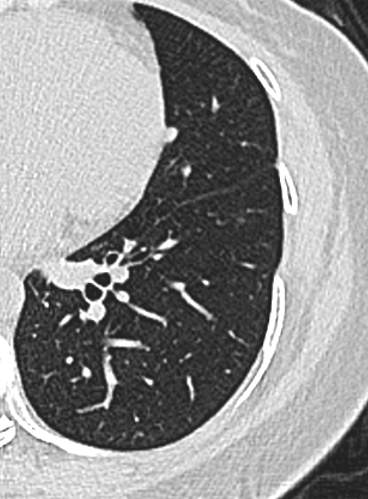

中年女性,既往体健。

21年底左下肺,直径5.2mm:

23年初复查CT左下肺GGO有所增大,直径:6.9mm